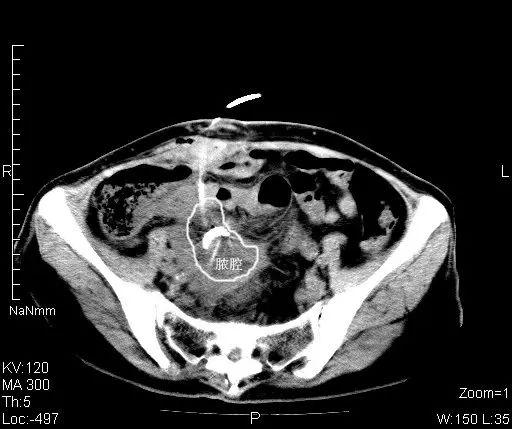

影像科穿刺团队郝申、张勇猛医师阅片后发现,此处脓肿位于盆腔深部,前方肠管横跨,几乎无进针路径;后方及侧方髂骨及骶骨遮挡,无法进针。

遂选择同轴活检针,将内芯抽出,只用无尖锐的钝头缓慢进针并注射生理盐水,试图冲开前方肠管,寻觅间隙,打开通道。最终成功置入导管,引流出黄褐色脓液,引流通畅,患者安全返回病房。